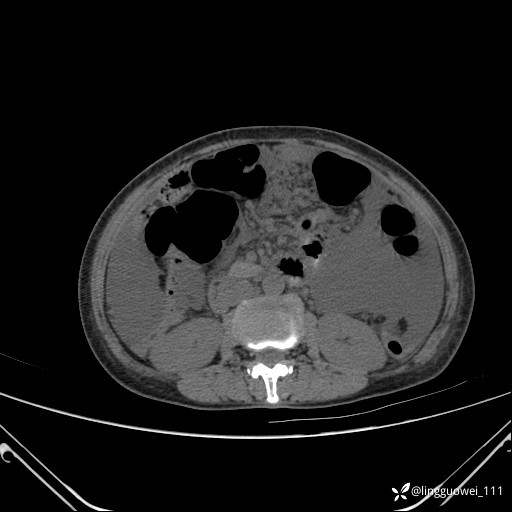

病例女,65岁,门诊行胃肠镜检查后,说腹胀入院检查,CT能发现病因吗?已公布结果

主诉:门诊行胃肠镜检查后,诉腹胀,入院检查,肝有病变吗?腹膜及腹腔的表现有特征性吗?

平扫: